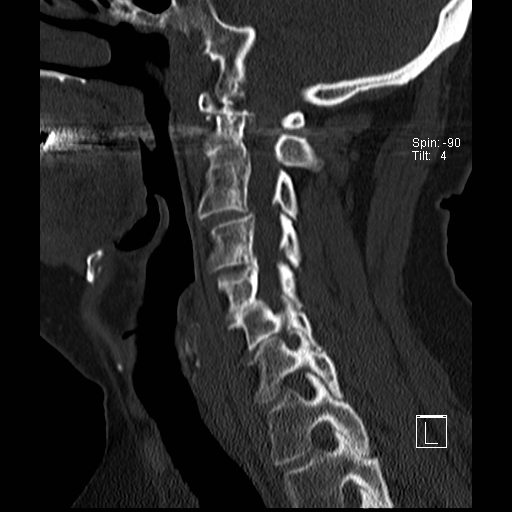

Lồng nền sọ

Lồng nền sọ, còn gọi là sụt lún sọ não hay ấn nền sọ, xảy ra ở 5-10% bệnh nhân viêm khớp dạng thấp cột sống cổ.

Trong lồng nền sọ, mỏm răng sa vào lỗ chẩm làm thu hẹp không gian dành cho tủy sống.

Biểu hiện lâm sàng đa dạng, từ đau đầu mạn tính, hạn chế vận động cổ đến suy giảm thần kinh cấp tính (chèn ép tủy sống và thân não, có thể dẫn đến liệt hoặc thậm chí tử vong nếu cổ bị di chuyển ở một số tư thế nhất định).

Hình ảnh

Cuộn xem các lát cắt CT.

Có hình ảnh di chuyển lên trên của mỏm răng vào lỗ chẩm.